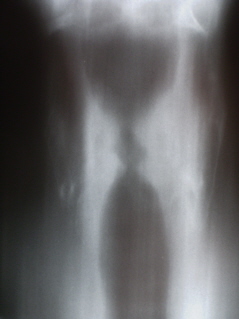

Рентгенологическое исследование гортани - томография проведено по стандартной методике (на РДК на 3 рабочих места – «Вироматик».

На томограммах гортани (иллюстрации 3, 4) определяется деформация гортани, с резким утолщением её стенки слева, выражена асимметрия надсвязочного и связочного пространств, с выраженной нечёткостью и деформацией контура стенки надсвязочного пространства слева.

4.